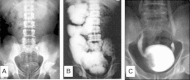

In this review, the clinical manifestations of urinary schistosomiasis are displayed from a pathogenetic perspective. According to the prevailing host's immune response profile, urinary schistosomiasis may be broadly categorized into cell-mediated and immune-complex-mediated disorders. The former, usually due to Schistosoma haematobium infection, are attributed to the formation of granulomata along the entire urinary tract. As they heal with excessive fibrosis, they may lead to strictures, calcifications and urodynamic abnormalities. The main impact is lower urinary, the site of heaviest ovi-position. Secondary bacterial or viral infection is common, any may be incriminated in secondary stone formation of the development of bladder malignancy. Immune-complex mediated lesions are usually associated with hepatosplenic schistosomiasis due to Schistosoma mansoni infection. Circulating complexes composed of schistosomal gut antigens and different classes of immunoglobulins deposit in the kidneys leading to several patterns of glomerular pathology. The latter have been categorized under six classes based on the histological and immunofluorescence profile. These classes have been linked to respective clinical manifestations and depend on the stage of evolution of the host's immune response, extent of associated hepatic fibrosis and co-infection with salmonella or hepatitis C. Secondary amyloidosis develops in 15% of such patients, representing a critical impairment of macrophage function.